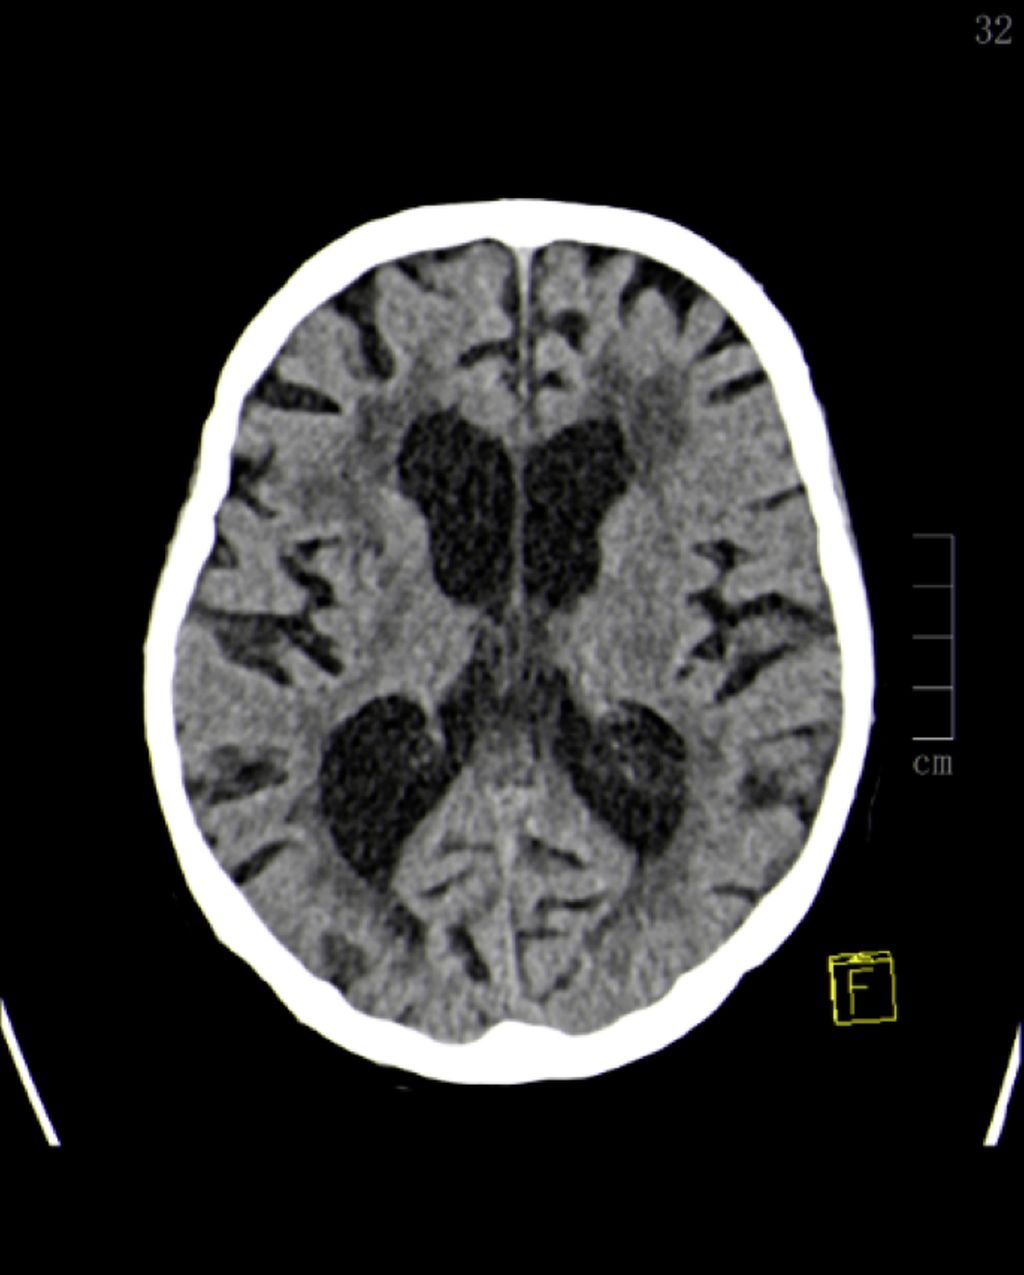

Abb. 2: Unauffälliges CCT einer 82-jährigen Patientin mit einer Schädelprellung unter der Einnahme von Edoxaban (Lixiana®)

Bemerkenswert ist, dass bei der oben erwähnten Patientengruppe in der Diagnostik nahezu ausnahmslos an der kranialen Computertomografie (CCT) (Abb.2) festgehalten wird. Diese radiologische Abklärung ist aus Sicht der aktuellen Literatur zu hinterfragen und zu reevaluieren.9,12 Selbst Colas et al. stellten in ihrer Arbeit die Frage nach dem Benefit einer standardisierten Computertomografie bei Patient*innen mit leichtem SHT, da sie ein gleiches Outcome bei Patient*innen mit und ohne eine in der CCT detektierte intrakranielle Blutung und Einnahme einer antithrombotischen Therapie feststellten.13